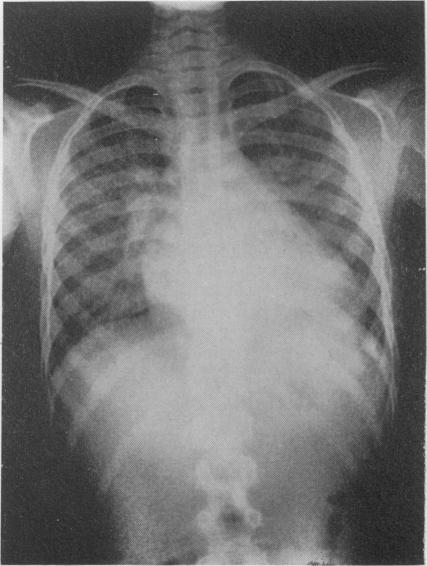

Rheumatic fever. A clinico-pathological conference held at the Royal Alexandra Hospital for Sick Children, Brighton, on Tuesday, 8 February 1966.

Postgrad Med J. 1967 Jul;43(501):467-80. doi: 10.1136/pgmj.43.501.467.